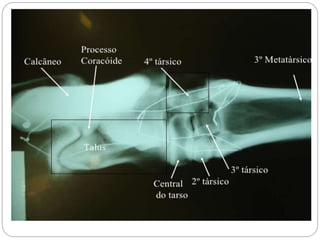

Figura – 1

Látero-lateral